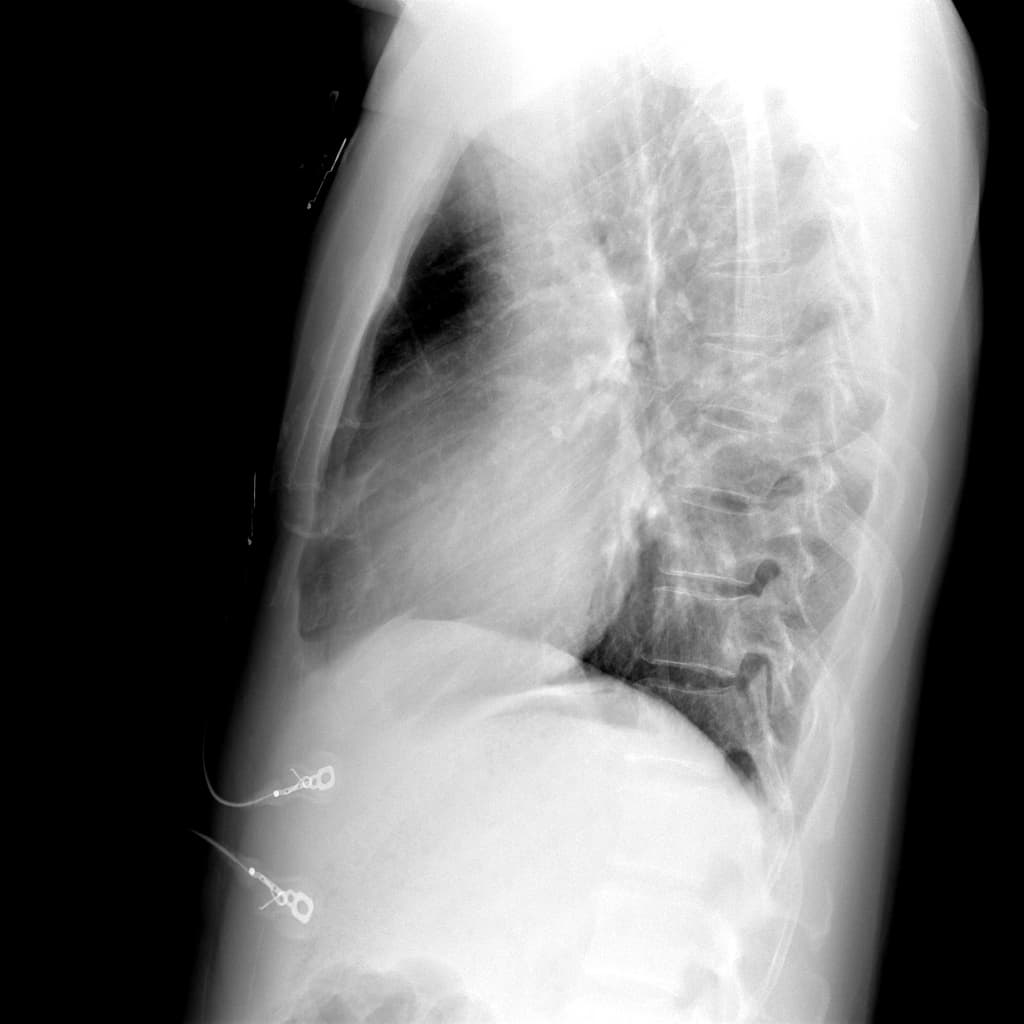

Tiền sử điều trị ung thư, chụp X-quang ngực theo dõi tái khám.

- Khối hình bầu dục ở thuỳ trên bên trái, các hình ảnh còn lại bình thường.